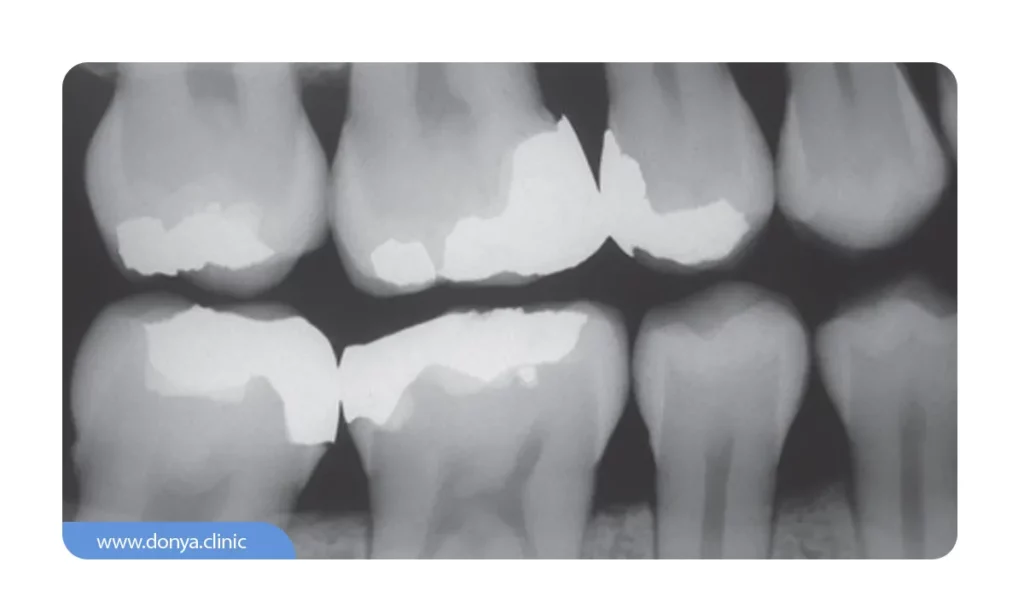

هدف از انجام رادیوگرافی عکس دندان بایت وینگ ارزیابی کیفیت سلامت روکش دندانی است. دندانپزشک از زاویه 90 درجه چپ و راست چهره بیمار تصویربرداری می کند تا وضعیت واحدهای دندانی عقب و آسیاب کوچک را در فکین فوقانی و تحتانی را بررسی نماید. اگر بخواهیم به زبان خیلی ساده تر صحبت کنیم؛ دندانپزشک با استفاده از این عکس تمام جزئیات واحدهای دندانی فک بالا و پایین از یک سمت خاص دندان (قسمت تاج) ارزیابی می کند.

تصویربرداری رادیوگرافی بایت وینگ به ارزیابی کیفیت برخی از خدمات ترمیمی دندان نظیر وضعیت بریج دندان یا پر کردگی واحدهای دندانی دچار پوسیدگی کمک بسزایی می کند.